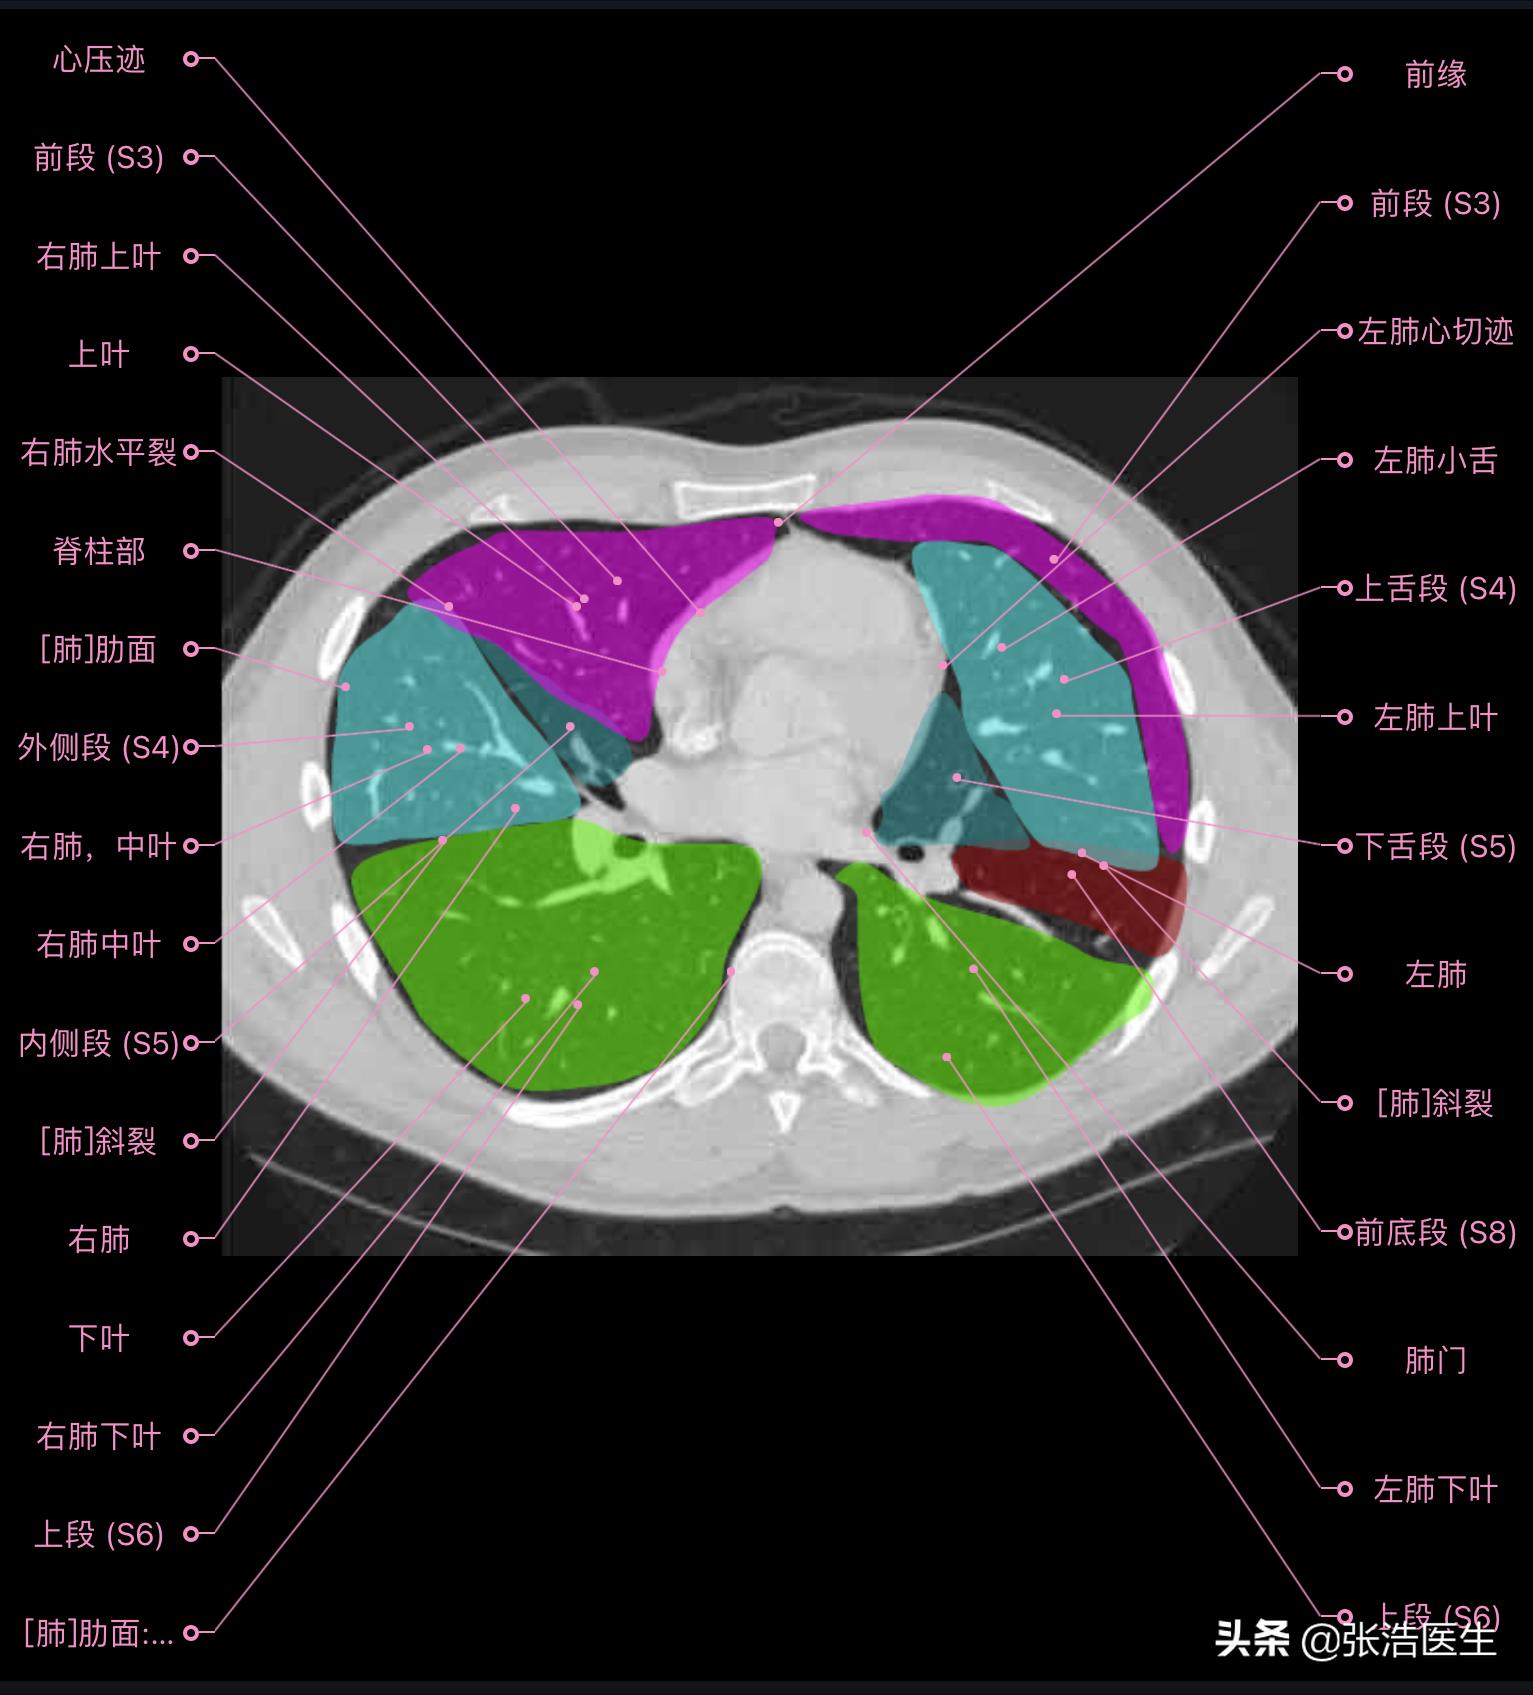

肺部CT横断面高清解剖图谱(图层4)